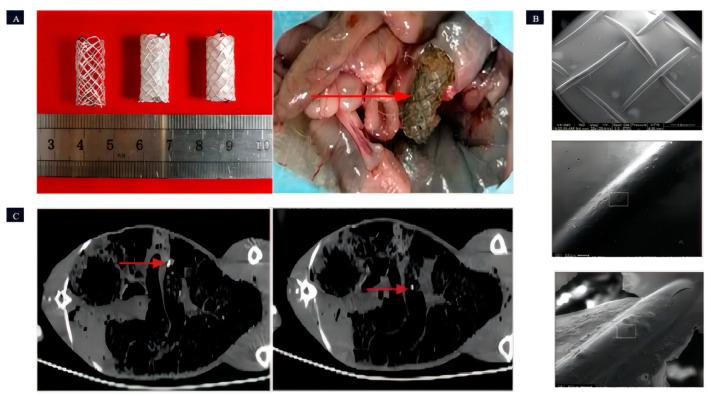

The human body comprises various tubular structures that have essential functions in different bodily systems. These structures are responsible for transporting food, liquids, waste, and other substances throughout the body. However, factors such as inflammation, tumors, stones, infections, or the accumulation of substances can lead to the narrowing or blockage of these tubular structures, which can impair the normal function of the corresponding organs or tissues. To address luminal obstructions, stenting is a commonly used treatment. However, to minimize complications associated with the long-term implantation of permanent stents, there is an increasing demand for biodegradable stents (BDS). Magnesium (Mg) metal is an exceptional choice for creating BDS due to its degradability, good mechanical properties, and biocompatibility. Currently, the Magmaris coronary stents and UNITY-B biliary stent have obtained Conformité Européene (CE) certification. Moreover, there are several other types of stents undergoing research and development as well as clinical trials. In this review, we discuss the required degradation cycle and the specific properties (anti-inflammatory effect, antibacterial effect, etc.) of BDS in different lumen areas based on the biocompatibility and degradability of currently available magnesium-based scaffolds. We also offer potential insights into the future development of BDS.